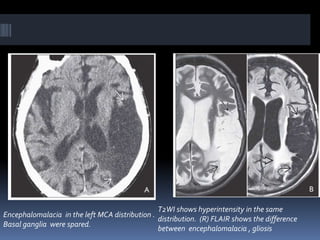

Encephalomalacia in the left MCA distribution .

Basal ganglia were spared.

T2WI shows hyperintensity in the same

distribution. (R) FLAIR shows the difference

between encephalomalacia , gliosis